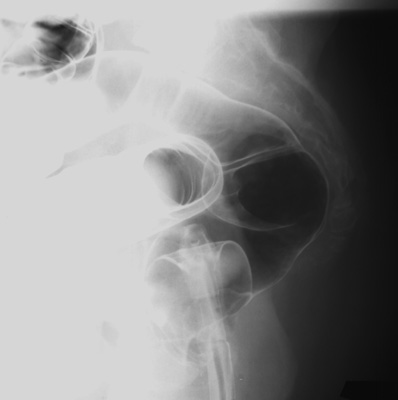

Rotate the patient back into LPO position. Take spot image

of hepatic flexure.

- Rotate the patient into RPO position.

Take spot image of splenic flexure.